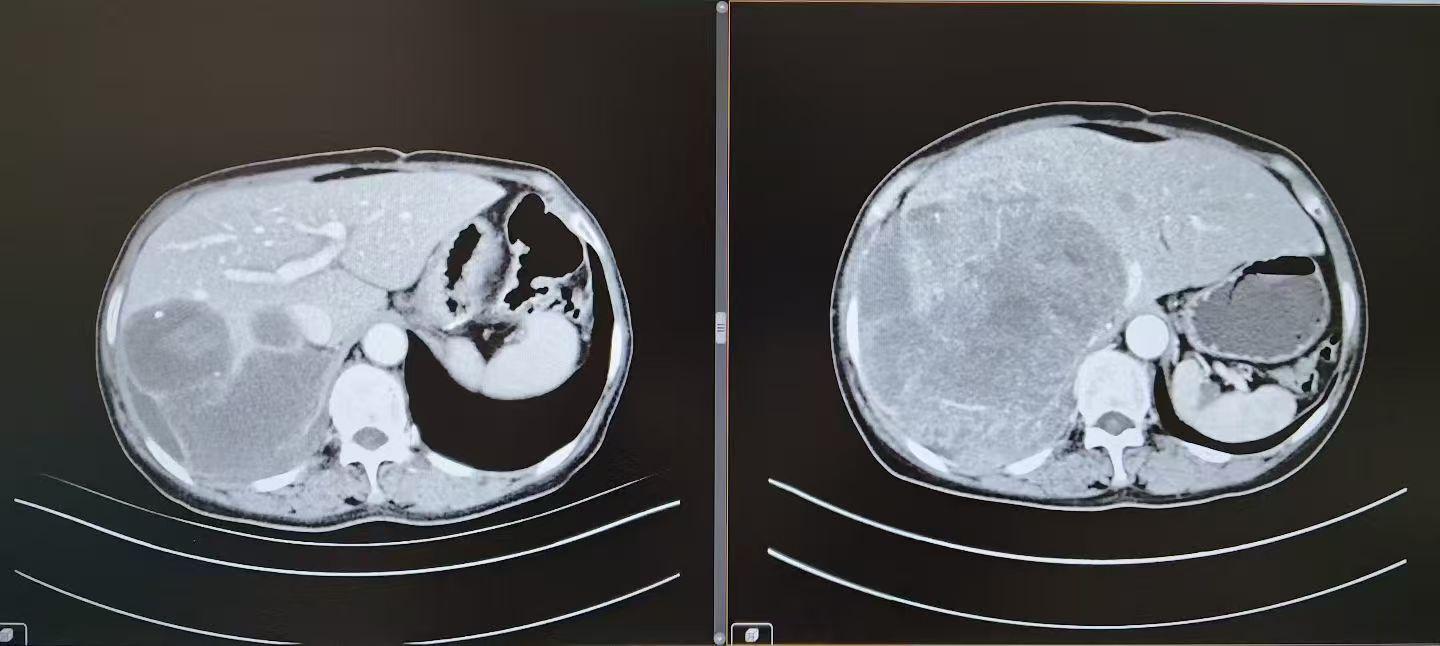

胸部+腹部增强ct

肿瘤巨大,且侵蚀侵犯重要脏器。接诊后,杨诏旭教授团队立即对李霞的病情展开全面评估。阅片结果显示:肿瘤已侵犯右半肝、右下肺、右肾等多脏器,与心脏、下腔静脉紧密粘连且生长迅速,然而常规手术面临多重致命风险:剩余肝脏体积不足难以支撑术后功能,肿瘤与心脏大血管粘连紧密易引发大出血,肺叶切除与胸腹腔联合操作复杂度极高。